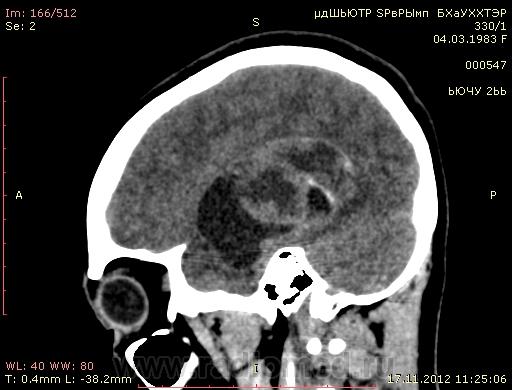

Молодая женщина, 29 лет. Обратилась на прием к неврологу 26.10.12г с  болями в шее, назначено лечение амбулаторно по сосудистой головной боли, остеохондрозу.. После 14.11.12г обратилась к другому неврологу повторно, 16.11.12г направлена в стационар. Жалобы: на снижение зрения, головные боли, головокружения, слабость, повышение температуры. Провели СКТ головного мозга натив и контрастирование. Подскажите пожалуйста, коллеги- Это опухоль? тогда какая (глиобластома, невринома, менингиома?) и локализацию. Спасибо.

Сканы с контрастированием.

Нативное исследование.

Одно можно сказать точно: это не менингиома и не невринома (у тех структура однородная). Это Вам в помощь http://www.radiologyassistant.nl/en/p47f86aa182b3a/brain-tumor-systematic-approach.html

Мне кажется, что тут субэпендимарная глиома. Указываете степень дислокации, накопления и к нейрохирургам.

Согласна с Андреем Юрьевичем. Все остальное возможно, в том числе олигодендроглиома. Впрочем не принципиально. К нейрохирургам!

Только что узнала результаты вскрытия.Гистология пока не готова.

Глиобластома с прорастанием стенки правого бокового желудочка, выраженный отек, смещение срединных структур, вклинение миндалин мозжечка в БЗО.